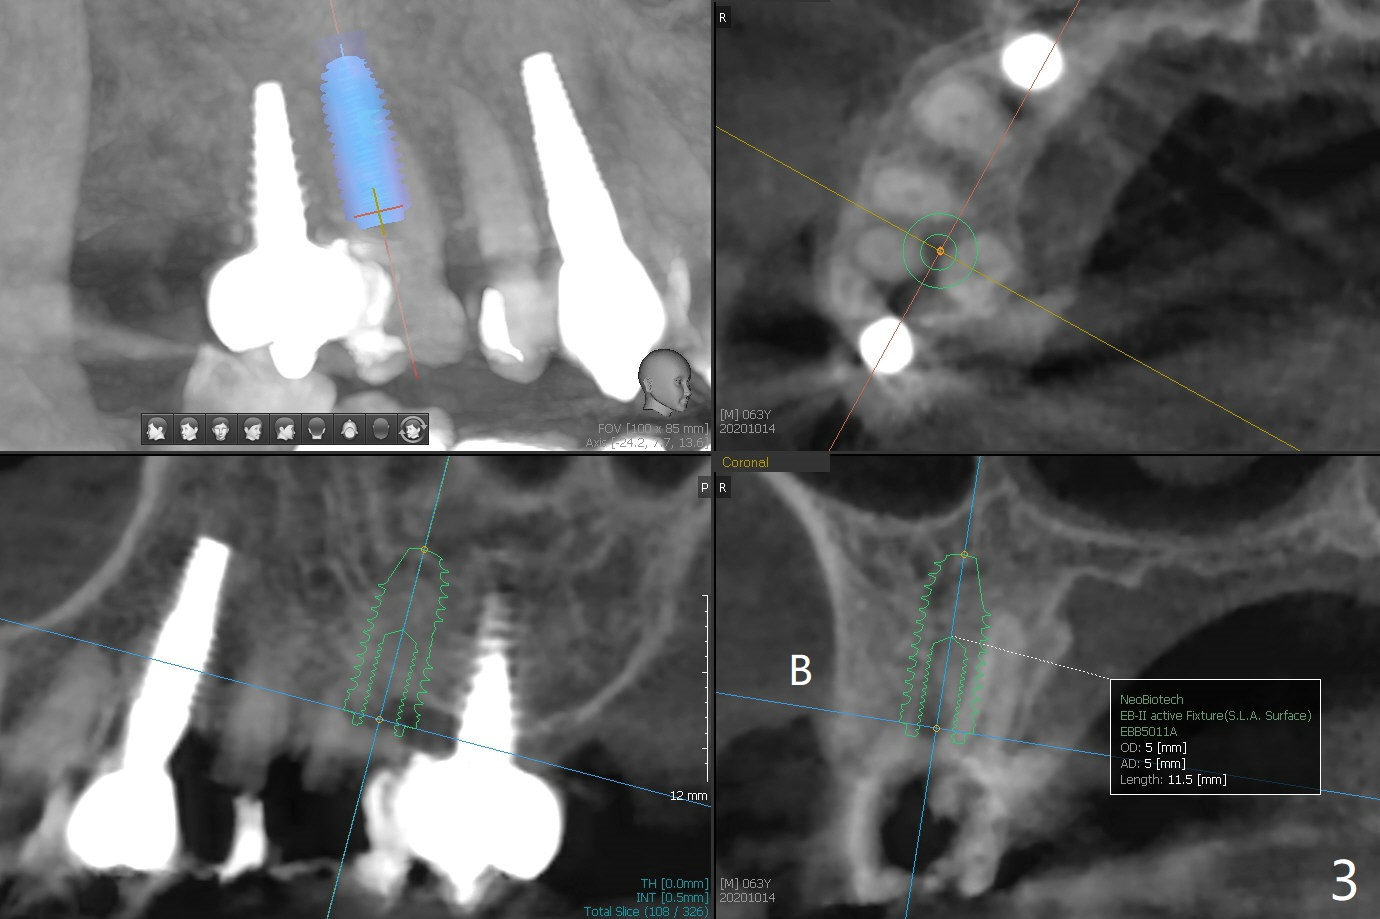

63岁女右上6远中龋齿在邻牙植牙牙冠粘固后2年8个月坏的严重(图一),病人决定拔除种植。之前嘱咐她回来修复,部分由于新冠病毒,她拖延治疗。今后需要建立一个植牙后完整随访和严密检查系统,减少继发龋。分析四个植牙(图二,四至六)表明骨质宽度优越,右上6即刻种植应该没问题(图三)。植体选择与邻近一致。Prevent Molar Periimplantitis (Protocols, Table) No Neighboring Caries Metronidazole Magicore Cases 手术 2 Xin Wei, DDS, PhD, MS 1st edition 10/14/2020, last revision 11/17/2020